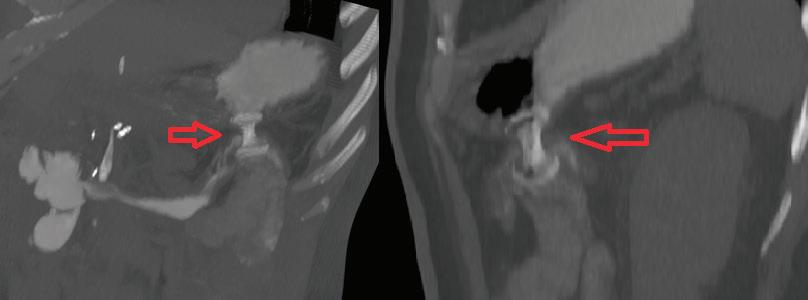

след чер нодробна трансплатация Фиг. 7 ЕРХПГ

поставени два пластма сови стента

ране.

СТРИКТУРИ ТИП 4 Тип 4 са хирургични анастомози, като хепатико-йеюноанастомоза, които могат да бъдат предизвика телство за терапия поради промене на анатомия. Традиционно подходът е перкутанен трансхепатален билиа рен дренаж (PTBD), но ако центърът има опит и наличност, ERCP също е привлекателна и най-минимално инвазивна опция. При тези пациенти може да бъде обсъден ехо-ендос копски навигиран билиарен дре наж[24] (Фиг. 7).